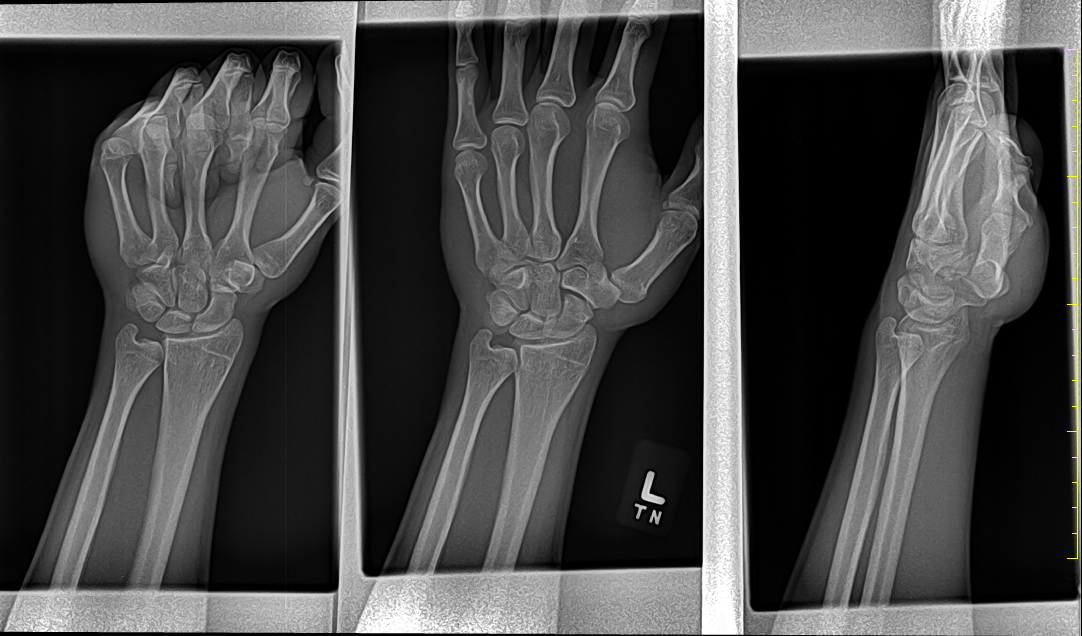

I honestly figured my growth plates would be closed since im 19...

any point in still taking my hgh for jaw/frame gains?